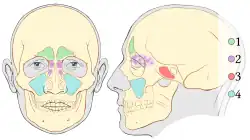

1. Senos frontales,

2. Senos etmoides,

3. Senos esfenoides,

4. Senos maxilares